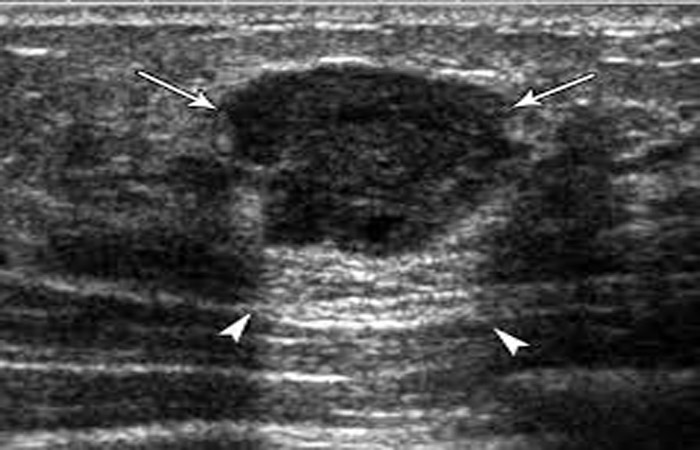

Συμπληρωματικά προς την υπερηχογραφική εκτίμηση λειτουργεί η ελαστογραφία. Πρόκειται για μία σχετικά πρόσφατη τεχνική στον υπερηχογραφικό έλεγχο, η οποία συμβάλει στον προσδιορισμό – εκτίμηση της ελαστικότητας των ιστών (κατά κανόνα αλλοιώσεις αυξημένης σκληρίας συνηγορούν υπέρ κακοήθειας).